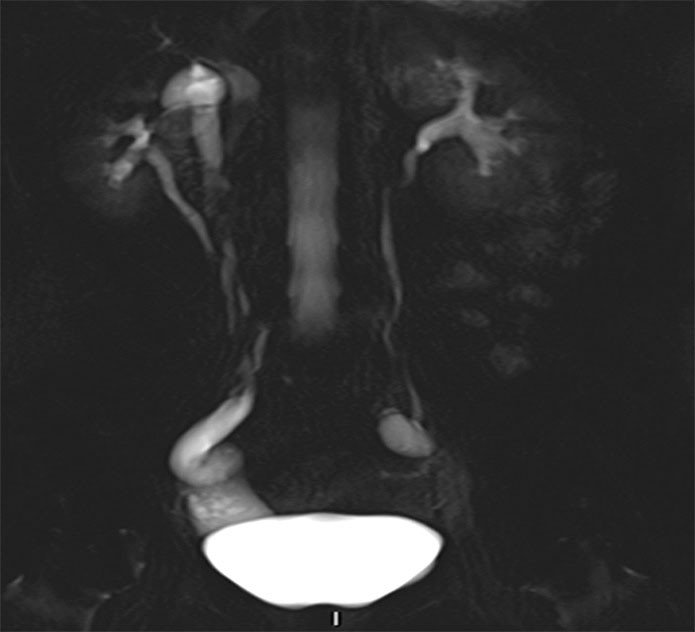

A CT scan of the urinary tract was performed, but proved inconclusive with respect to ureteral ectopia. MRI of the urinary tract was therefore performed in addition. This revealed a right-sided duplex collecting system with a small upper collecting system and a dilated ureter (Figure 1). The ureter was dilated from the bladder to the vagina and opened out ectopically near the urethral opening (Figure 2).

Figure 1 MRI. Coronal 50 mm thick section, T2-HASTE (Half-Fourier Acquisition Single-shot Turbo spin Echo imaging). A right…

Figure 1 MRI. Coronal 50 mm thick section, T2-HASTE (Half-Fourier Acquisition Single-shot Turbo spin Echo imaging). A right-sided duplex system can be seen, the upper system with moderate hydronephrosis, plus hydroureter in the pelvis.

Identification of a duplex collecting system and ectopic ureter on CT requires adequate function and contrast excretion from the upper collecting system, which was not the case in this patient. It is possible to detect a dilated ectopic ureter with ultrasound, but this can be difficult unless the condition is specifically looked for. Our patient was referred with suspected cholelithiasis and pyelonephritis, and no pathology was detected upon routine examination of the urinary tract. High-resolution fluid-sensitive volumetric MRI sequences are good for identifying the ureter and tracing its course. MRI is more appropriate than CT in the lesser pelvis, but more time-consuming. Dedicated high-resolution series in the pelvis were supplemented with less detailed sequences of the upper urinary tract. No contrast agent was used during the MRI scan. Paediatricians use MRI as the primary imaging modality upon suspicion of ureteral ectopia.